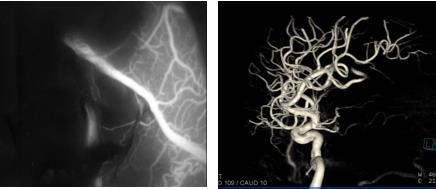

手术中,首先在神经导航下精准定位畸形血管团位置,然后根据术前多模态重建影像保护语言区脑组织,找到供血动脉,最后完整切除畸形血管团。双荧光手术显微镜荧光造影及MRI-DSA双杂交手术室术中脑血管造影(DSA)均显示血管畸形团已被全部切除。

术后显微镜荧光造影及杂交手术室脑血管造影(DSA)显示血管畸形团全切